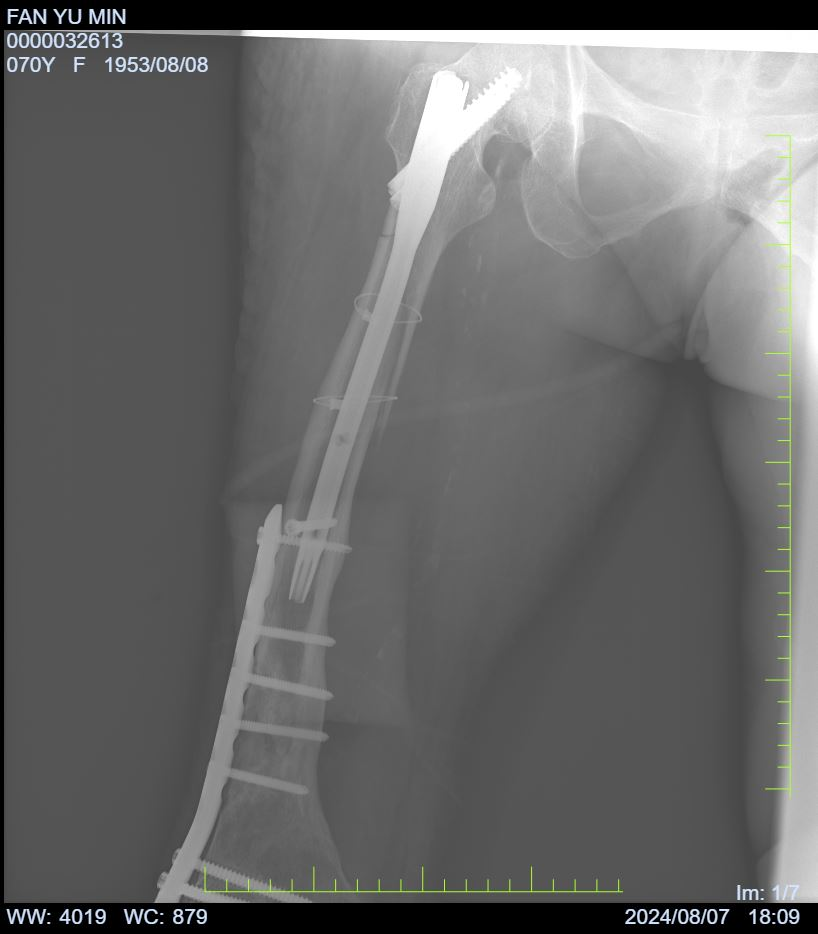

2024年8月3日,由骨科李贵主任主刀,在骨科团队的辅助下,顺利为范奶奶实施了精准的右侧股骨切开内固定装置去除术(针对部分螺钉)及股骨髓内钉内固定术。手术过程中,骨科与手术室(麻醉科)医护人员紧密协作,手术圆满成功。范奶奶术后状况稳定,且经C臂机透视确认右侧股骨髓内钉复位及内固定位置均理想,最终平安返回病房。

术后恢复期间,患者床旁摄片复查显示,右侧股骨髓内钉复位及内固定位置保持良好。范奶奶及其家属对手术结果表示高度满意,对我院的医疗技术和护理服务给予了充分的肯定。